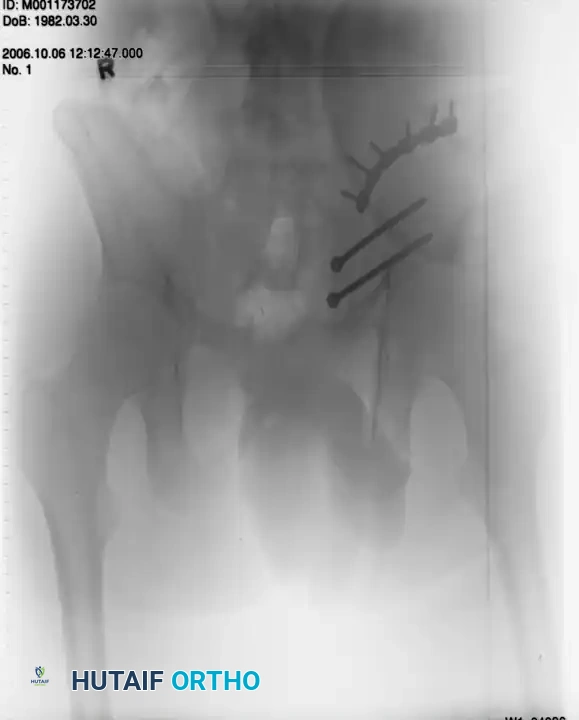

Surgical Management:

Treatment typically involves anterior fixation. The patient is positioned supine. A Pfannenstiel approach is utilized to access the symphysis. A multi-hole symphyseal plate is applied with alternating fully threaded cortical screws to reduce and stabilize the diastasis.

Postoperative Imaging:

Postoperative AP, inlet, and outlet views confirm anatomic reduction of the anterior ring and restoration of pelvic volume.

FIGURE 56-43: Young and Burgess anteroposterior type II (AP II) pelvic ring injury with pubic diastasis treated with anterior fixation. A and B, Preoperative views. C-E, Postoperative anteroposterior, inlet, and outlet views.